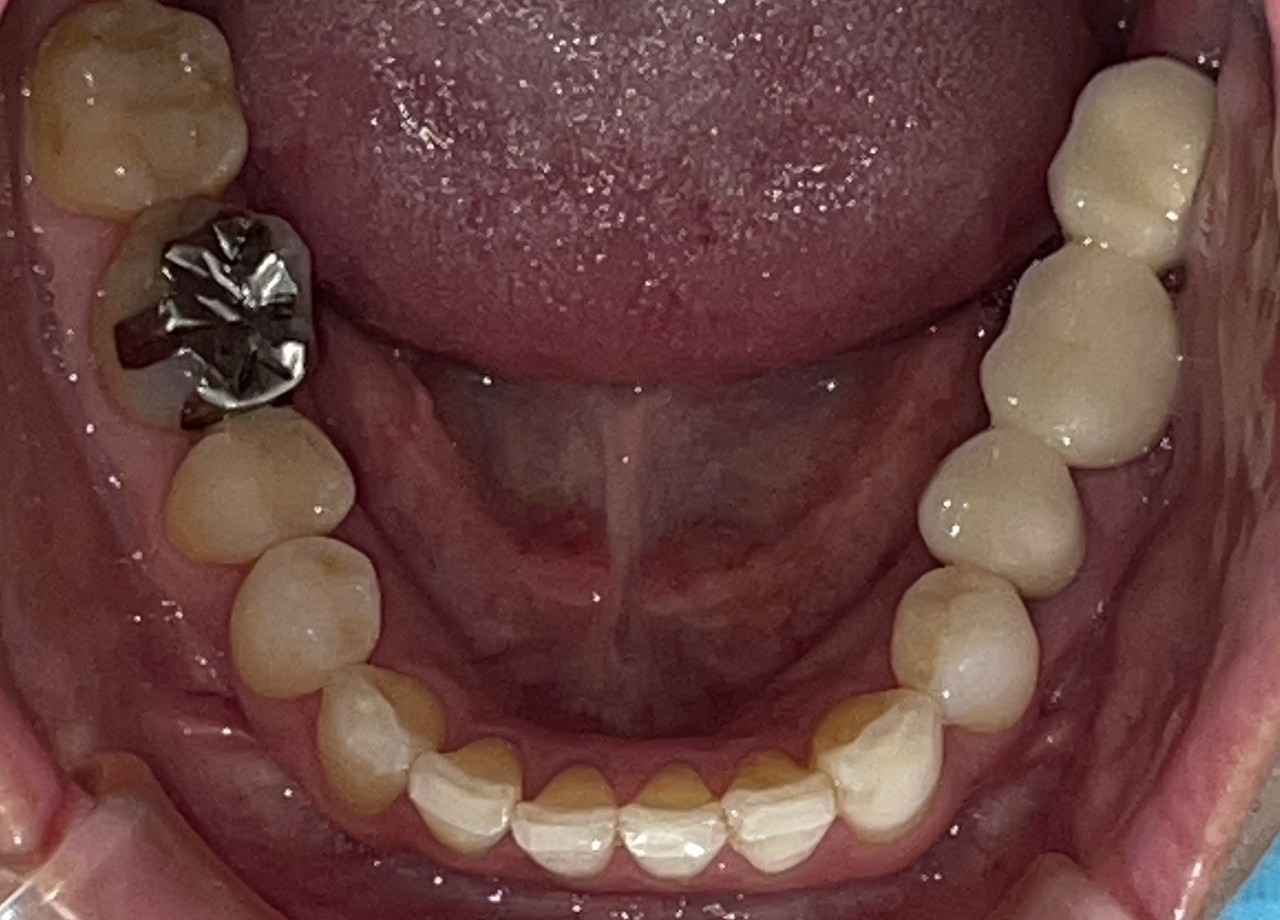

Before

After

矯正の種類 / invisalign GO

年齢・性別 / 30代男性

主訴  /  下の歯の叢生、オーバージェット、交叉咬合

治療期間 / 12ヶ月

費用 / 簡易検査 5,000円(税別) 精密検査 30,000円(税別)

両額マウスピース 450,000円(税別) 両額リテイナー料 40,000円(税別)

※マウスピース交換時別途調節料5,000円(税別)

副作用 / 口内炎・歯の移動に伴う痛み・知覚過敏 ※数日で収まる場合が多いです

リスク / 後戻り防止の為、夜のみマウスピースで保定を指示